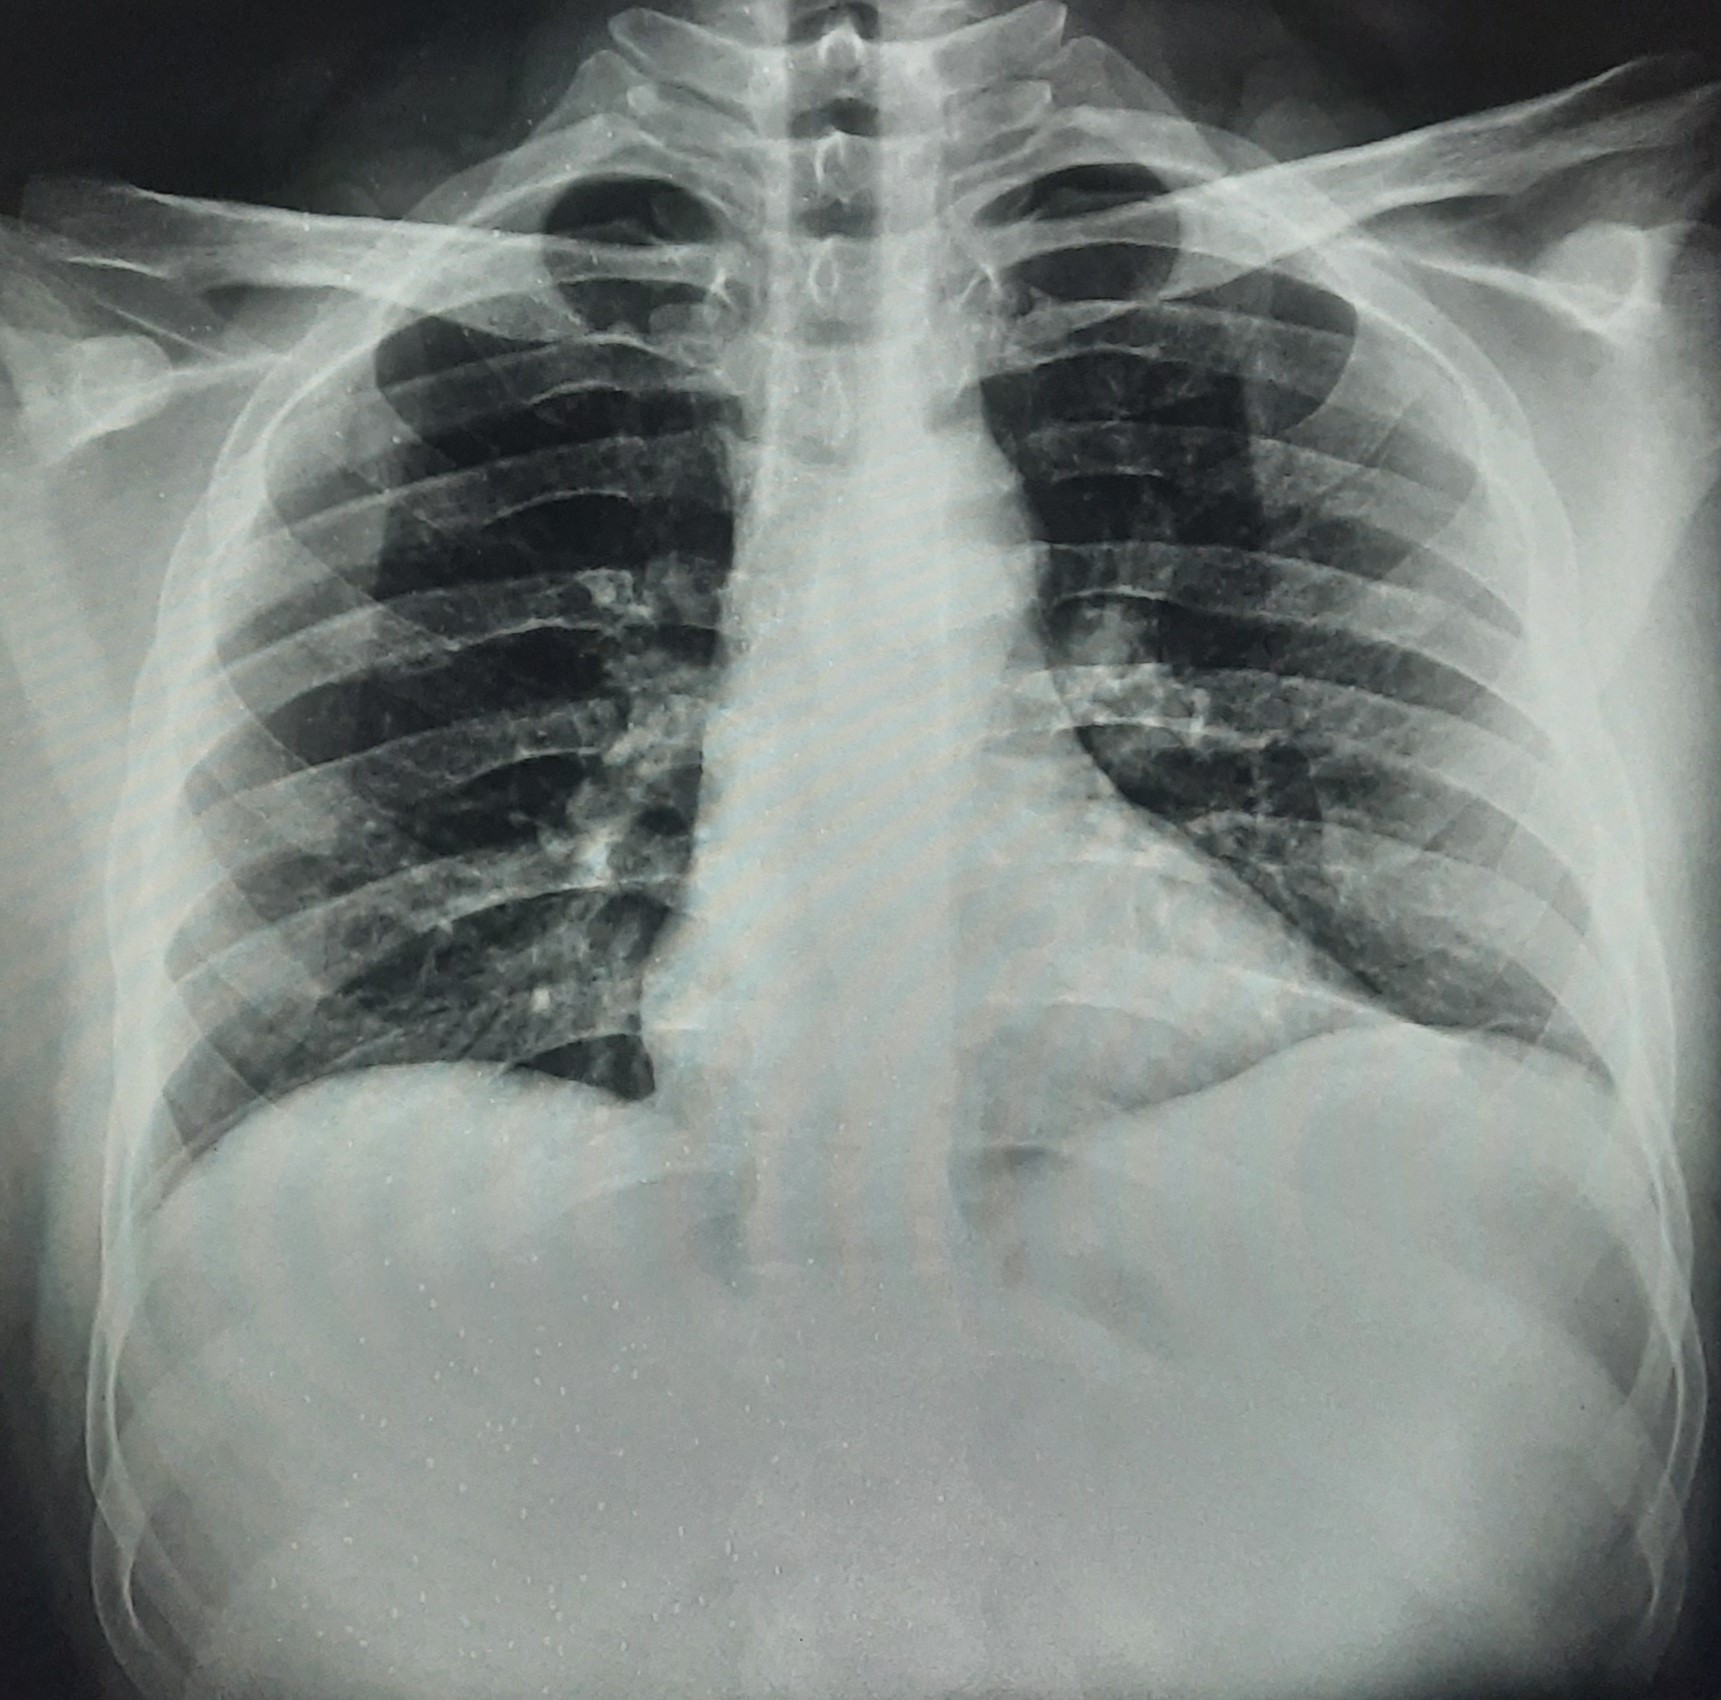

| 262 | IGGMC, Nagpur, Nagpur | P2 | 29-4210 | Mohamad Aslam | Consent taken on Paper | 35 Yrs. |

Provisional Diag : C/O Extra Pulmonary TB

Final Diag : FIBROSIS |

TB Case (Confirmed) | S/O RETICULAR OPACITIES NOTED IN RIGHT UPPER & MIDDLE ZONE/ QUERY FIBROSIS | Abnormality visible on x-ray |